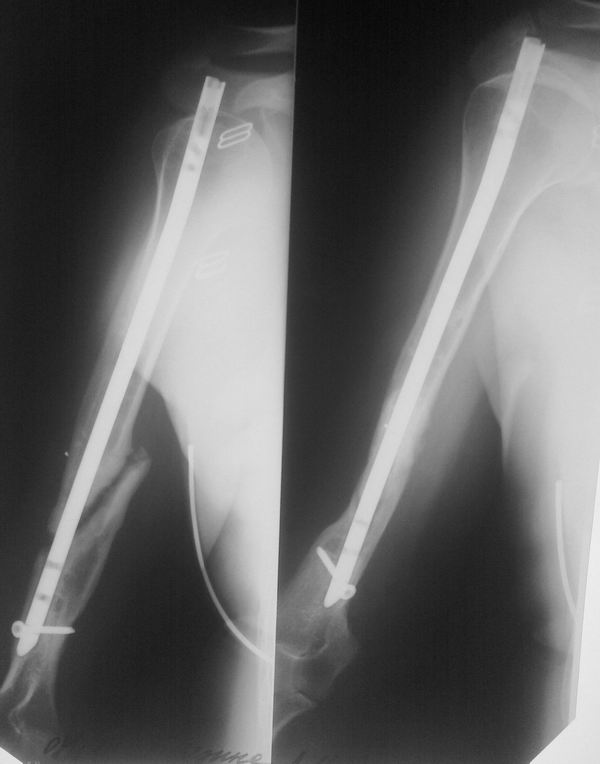

Снимки в динамике